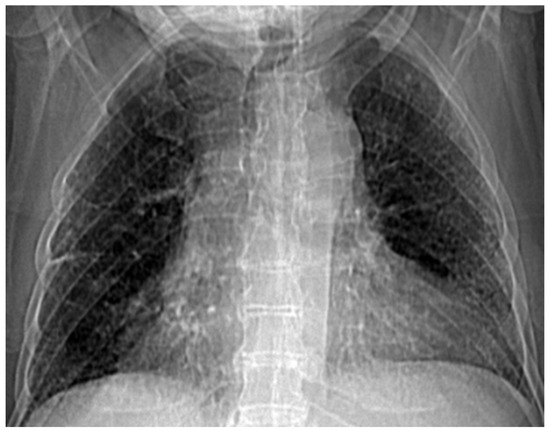

In this paper, pulmonary radiological images obtained using CT techniques were investigated. Postero-anterior lung radiographs with macronodular opacity (<2 cm), of costal intensity, homogeneously located in the lower half of the lung field, were analyzed using known fractal indicators (fractal dimension and lacunarity) [21].

Several patients with a preliminary diagnosis of COVID-19 were tested using CT imaging with the contrast substance OMNIPAQUE 350. The pulmonary CT images obtained for each patient, along with their detailed fractal analysis, are presented in Figure 1, below.

Figure 1. (a) The CT scan image of a 69-year-old patient who underwent a chest CT examination due to suspicion of COVID-19 in the lungs. (b) A schematic representation of the pre-processing phases of the patient’s CT image (2D), which was resampled to an isomorphic resolution. The indices 5, 14, and 16 represent the numbers of the slices in order.